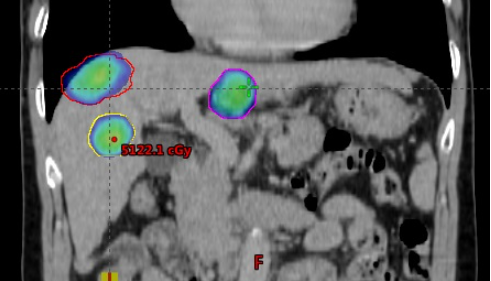

| Xạ trị SBRT điều trị đồng thời 3 khối u gan - Nguồn: Khoa Xạ trị - Xạ phẫu, Bệnh viện Trung ương Quân đội 108 |

SBRT là phương pháp điều trị không xâm lấn, sử dụng chùm bức xạ photon để phá hủy khối u. Hơn nữa, do xạ trị SBRT kiểm soát được di động khối u gan và thực hiện dưới hướng dẫn hình ảnh nên cho phép điều trị chính xác khối u trong khi vẫn bảo vệ được các cơ quan lành.

Phương pháp này có thể điều trị nhiều khối u cùng một lúc và đặc biệt có ưu thế đối với khối u gan nằm ở những vị trí RFA khó thực hiện. Hơn nữa, SBRT là phương pháp điều trị an toàn với tác dụng phụ tối thiểu khi được chỉ định đúng và tiến hành ở các trung tâm xạ trị lớn có đội ngũ nhân viên y tế trình độ cao, giàu kinh nghiệm với đầy đủ trang thiết bị cho phép thực hiện kỹ thuật.